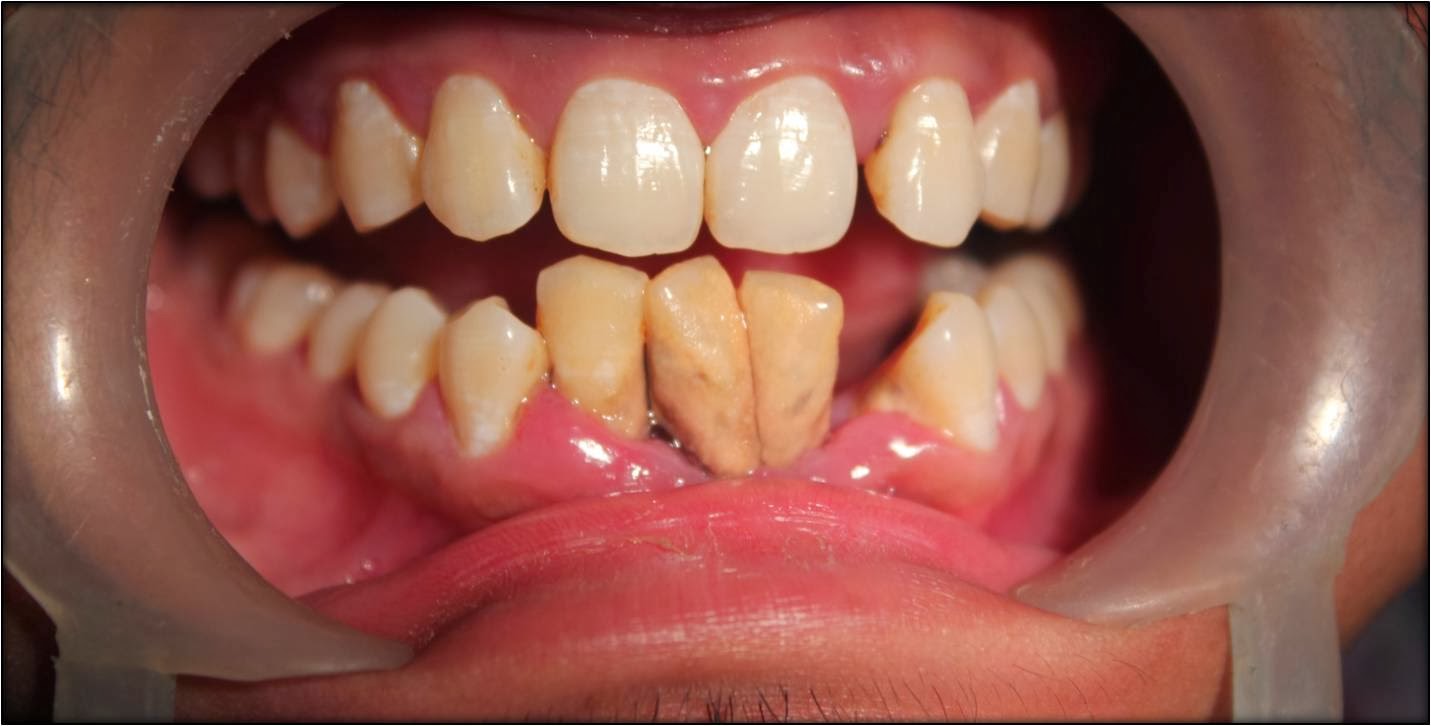

Picture showing severe plaque, calculus , tartar with severe gaps..

Patient came with the complaint of shaking lower front teeth due to improper maintenance of oral hygiene .This is a form aggressive gum disease and also because of the severe diabetic condition of the patient at younger age.